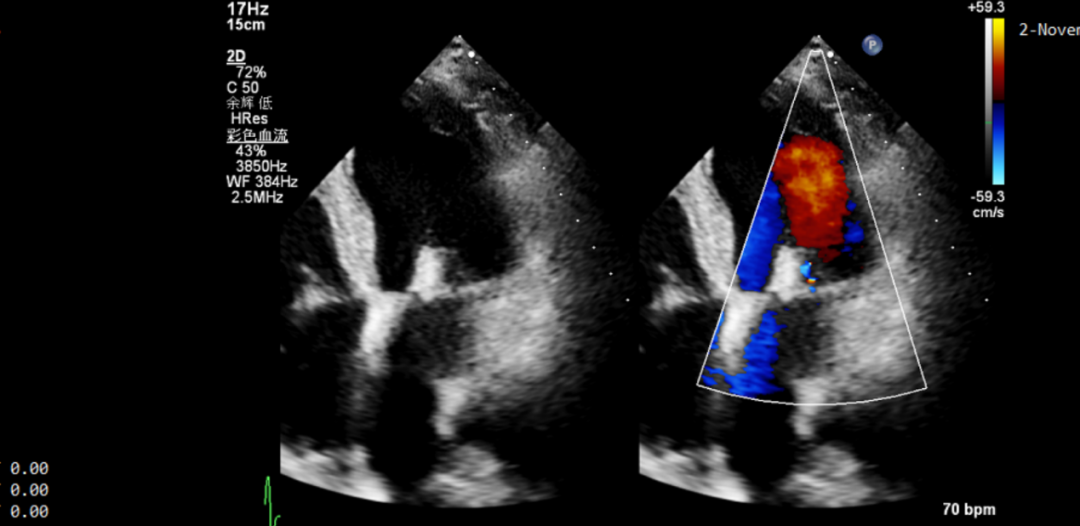

77岁的朱爷爷患心脏病多年,胸闷,喘累,气促伴咳嗽两月余,5天前突然加重,遂至当地医院就诊,考虑“肺部感染”,治疗4-5天症状无缓解,并出现双下肢水肿,建议上级医院就诊,遂至我院心内科门诊就诊,行TTE提示“左房,左室增大,二尖瓣稍增厚,后瓣脱垂,后瓣尖小腱锁断裂,重度反流”,行冠状动脉CT造影,未见冠脉管腔狭窄,随后行TEE评估提示“二尖瓣稍增厚,后瓣(P1区)腱索断裂,明显脱垂,重度反流,脱垂深度7.8mm,反流颈宽7.8mm”。(图1)

图1 患者一:TEE提示二尖瓣重度反流,P1区,腱索断裂